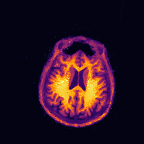

Multi-modality (or multi-channel) imaging is becoming increasingly important and more widely available, e.g. hyperspectral imaging in remote sensing, spectral CT in material sciences as well as multi-contrast MRI and PET-MR in medicine. Research in the last decades resulted in a plethora of mathematical methods to combine data from several modalities. State-of-the-art methods, often formulated as variational regularization, have shown to significantly improve image reconstruction both quantitatively and qualitatively. Almost all of these models rely on the assumption that the modalities are perfectly registered, which is not the case in most real world applications. We propose a variational framework which jointly performs reconstruction and registration, thereby overcoming this hurdle. Numerical results on simulated and real data show the potential of the proposed strategy for various applications in multi-contrast MRI, PET-MR, and hyperspectral imaging: typical misalignments between modalities such as rotations, translations, zooms can be effectively corrected during the reconstruction process. Therefore the proposed framework allows the robust exploitation of shared information across multiple modalities under real conditions.